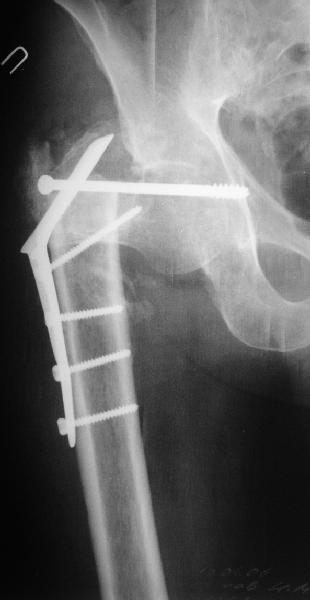

Уважаемые коллеги! Нужен совет.Больной Х., 21 год, ДЗ: ложный сустав вертельной области правого бедра.

Травма 8 мес. назад, ДТП, получил закрытый межвертельный перелом правого бедра. Лечился в городской больнице одного из городов-спутников г. Караганды скелетным вытяжением в течение 3 недель, затем кокситной гипсовой повязкой 2 мес. В настоящее время имеется укорочение конечности на 7 см, умеренная боль в вертельной области; ходит без костылей, полностью нагружая больную конечность, при нагрузке отмечается смещение дистального отломка проксимально примерно на 1,0 см.; объем движений в коленном суставе сохранен; при пальпации отломков боли нет, умеренная патологическая подвижность. Планируем внеочаговый остеосинтез спице-стержневым аппаратом, дистракция до восстановления длины бедра, вторым этапом остеосинтез стержнем Гамма. Есть надежда, что на дистракции пойдет сращение и у больного хватит терпения завершить лечение в аппарате.

По опыту подобных случаев, аппарат лучше на бедро, без таза пока. В проксимальный фрагмент 3 стержня по оси шейки. Дистальный - хватит 1 стержня или 2 спиц в дистальном метафизе и 1 стержня вверху. Если планируете гвоздь, надо с гиперкоррекцией восстановить длину и ось, т.е. вальгизировать проксимальный отдел. При наложении аппарата сделать остеоклазию, добиться уверенной подвижности. Регенерат не нужен, тяните на пределе переносимости пациентом - хоть 2 см/сут. Обычно меньше.

В приложении пример пациента, близкого по картине к тому, что представил Виктор (варус и смещение периферического отломка на поперечник кзади). Сделали как раз то, что Виктор исходно намеревался - аппаратная коррекция и затем гамма.